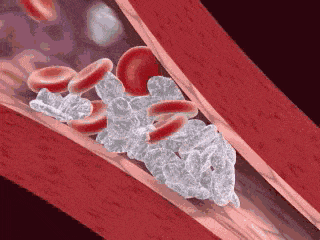

拔牙创的愈合关键点之一在于良好的创口封闭,封闭的关键在于拔牙窝内的血凝块。拔牙创内充满的血液约于15~30分钟即可形成血凝块而将创口封闭。此血块的存在有保护创口、防止感染、促进创口正常愈合的功能。吸烟时口腔内会形成负压环境,这样的环境下很容易把拔牙创内的血凝块吸出来,从而出血不止。

1)尼古丁使血液黏滞度增加、促进血小板聚集及内皮损伤,从而增加微血栓的形成,减少微循环灌流,可导致组织缺血。组织缺血、缺氧可致使表皮血管收缩,进而可导致肾上腺素和外周儿茶酚胺的释放,进一步增加了氧需要量。

2)尼古丁可激活颈动脉窦和主动脉体感受器,致使交感神经和肾上腺髓质释放儿茶酚胺;吸烟还可减少前列环素的合成、促进血管升压素和交感肾上腺介质的释放,使周围血管收缩,局部缺血。而局部缺血会让拔牙创血凝块形成量不足,拔牙窝封闭效果不佳,导致拔牙后创口的感染。